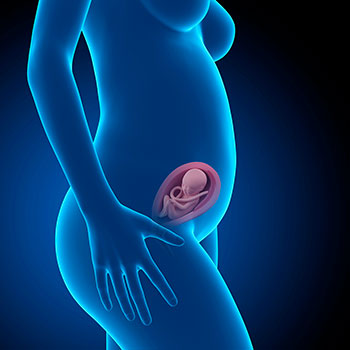

Na 23ª semana de gravidez, o bebé mede em média 28,9 centímetros desde o cocuruto até às nádegas e pesa à volta de 500 gramas.

Grávida de 23 semanas

Idade do feto: 21 semanas.

De certeza que tens vontade de ver como é, aproximadamente, o teu bebé durante esta semana. Aqui tens uma ecografia e um vídeo correspondentes à 23ª semana, para que o possas ver em movimento. Maravilhoso!

Na 23ª semana de gravidez o útero mede cerca de 22 centímetros e chega acima do umbigo. O teu peso deveria ter aumentado pouco mais de 4 kilos e meio.